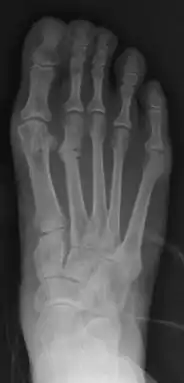

Bunion (hallux valgus) deformity is actually part of a complex of anatomical derangements of protruding mass (bunion), buckling of big toe (hallux valgus) and the bone behind it (metatarsus primus varus), displaced sesamoid bones (detrimental to the important walking function of big toe), collapsed metatarsal arch and several other secondary changes that are the domino effects of metatarsal primus varus. Thus, metatarsus primus varus correction has become the primary objective of all bunion surgeries.

Primus varus deformity

Primus varus deformity is the leaning of the first metatarsal bone away from the second metatarsal and towards the opposite foot (Fig. 1). As it leans over, its head sticks out to form the bunion bump and it also widens the forefoot to cause shoes feeling too tight. Thus when bunion pain becomes unmanageable, surgical correction is to narrow the forefoot by repositioning of the first metatarsal head back to its normal position. This can be done by osteotomy (bone-breaking), soft tissue (non-osteotomy) or fusion techniques.